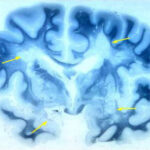

In uno studio su pazienti affetti da diabete di tipo 1, i ricercatori della Clinica Joslin, hanno scoperto che i grassi nella dieta possono influenzare i livelli di glucosio e di insulina. Questi risultati, che sono apparsi nel numero di aprile di Diabetes Care , hanno implicazioni importanti per la gestione del diabete di tipo 1.

La ricerca ha dimostrato che gli acidi grassi e grassi liberi (FFA) compromettono  la sensibilità all’insulina e glucosio aumentando la  produzione. La maggior parte degli studi si sono concentrati sul ruolo dei grassi nello sviluppo del diabete di tipo 2. Tuttavia, gli studi delle persone con diabete di tipo 1, hanno dimostrato che alto contenuto di grassi nei  pasti, può causare iperglicemia ore dopo il consumo.